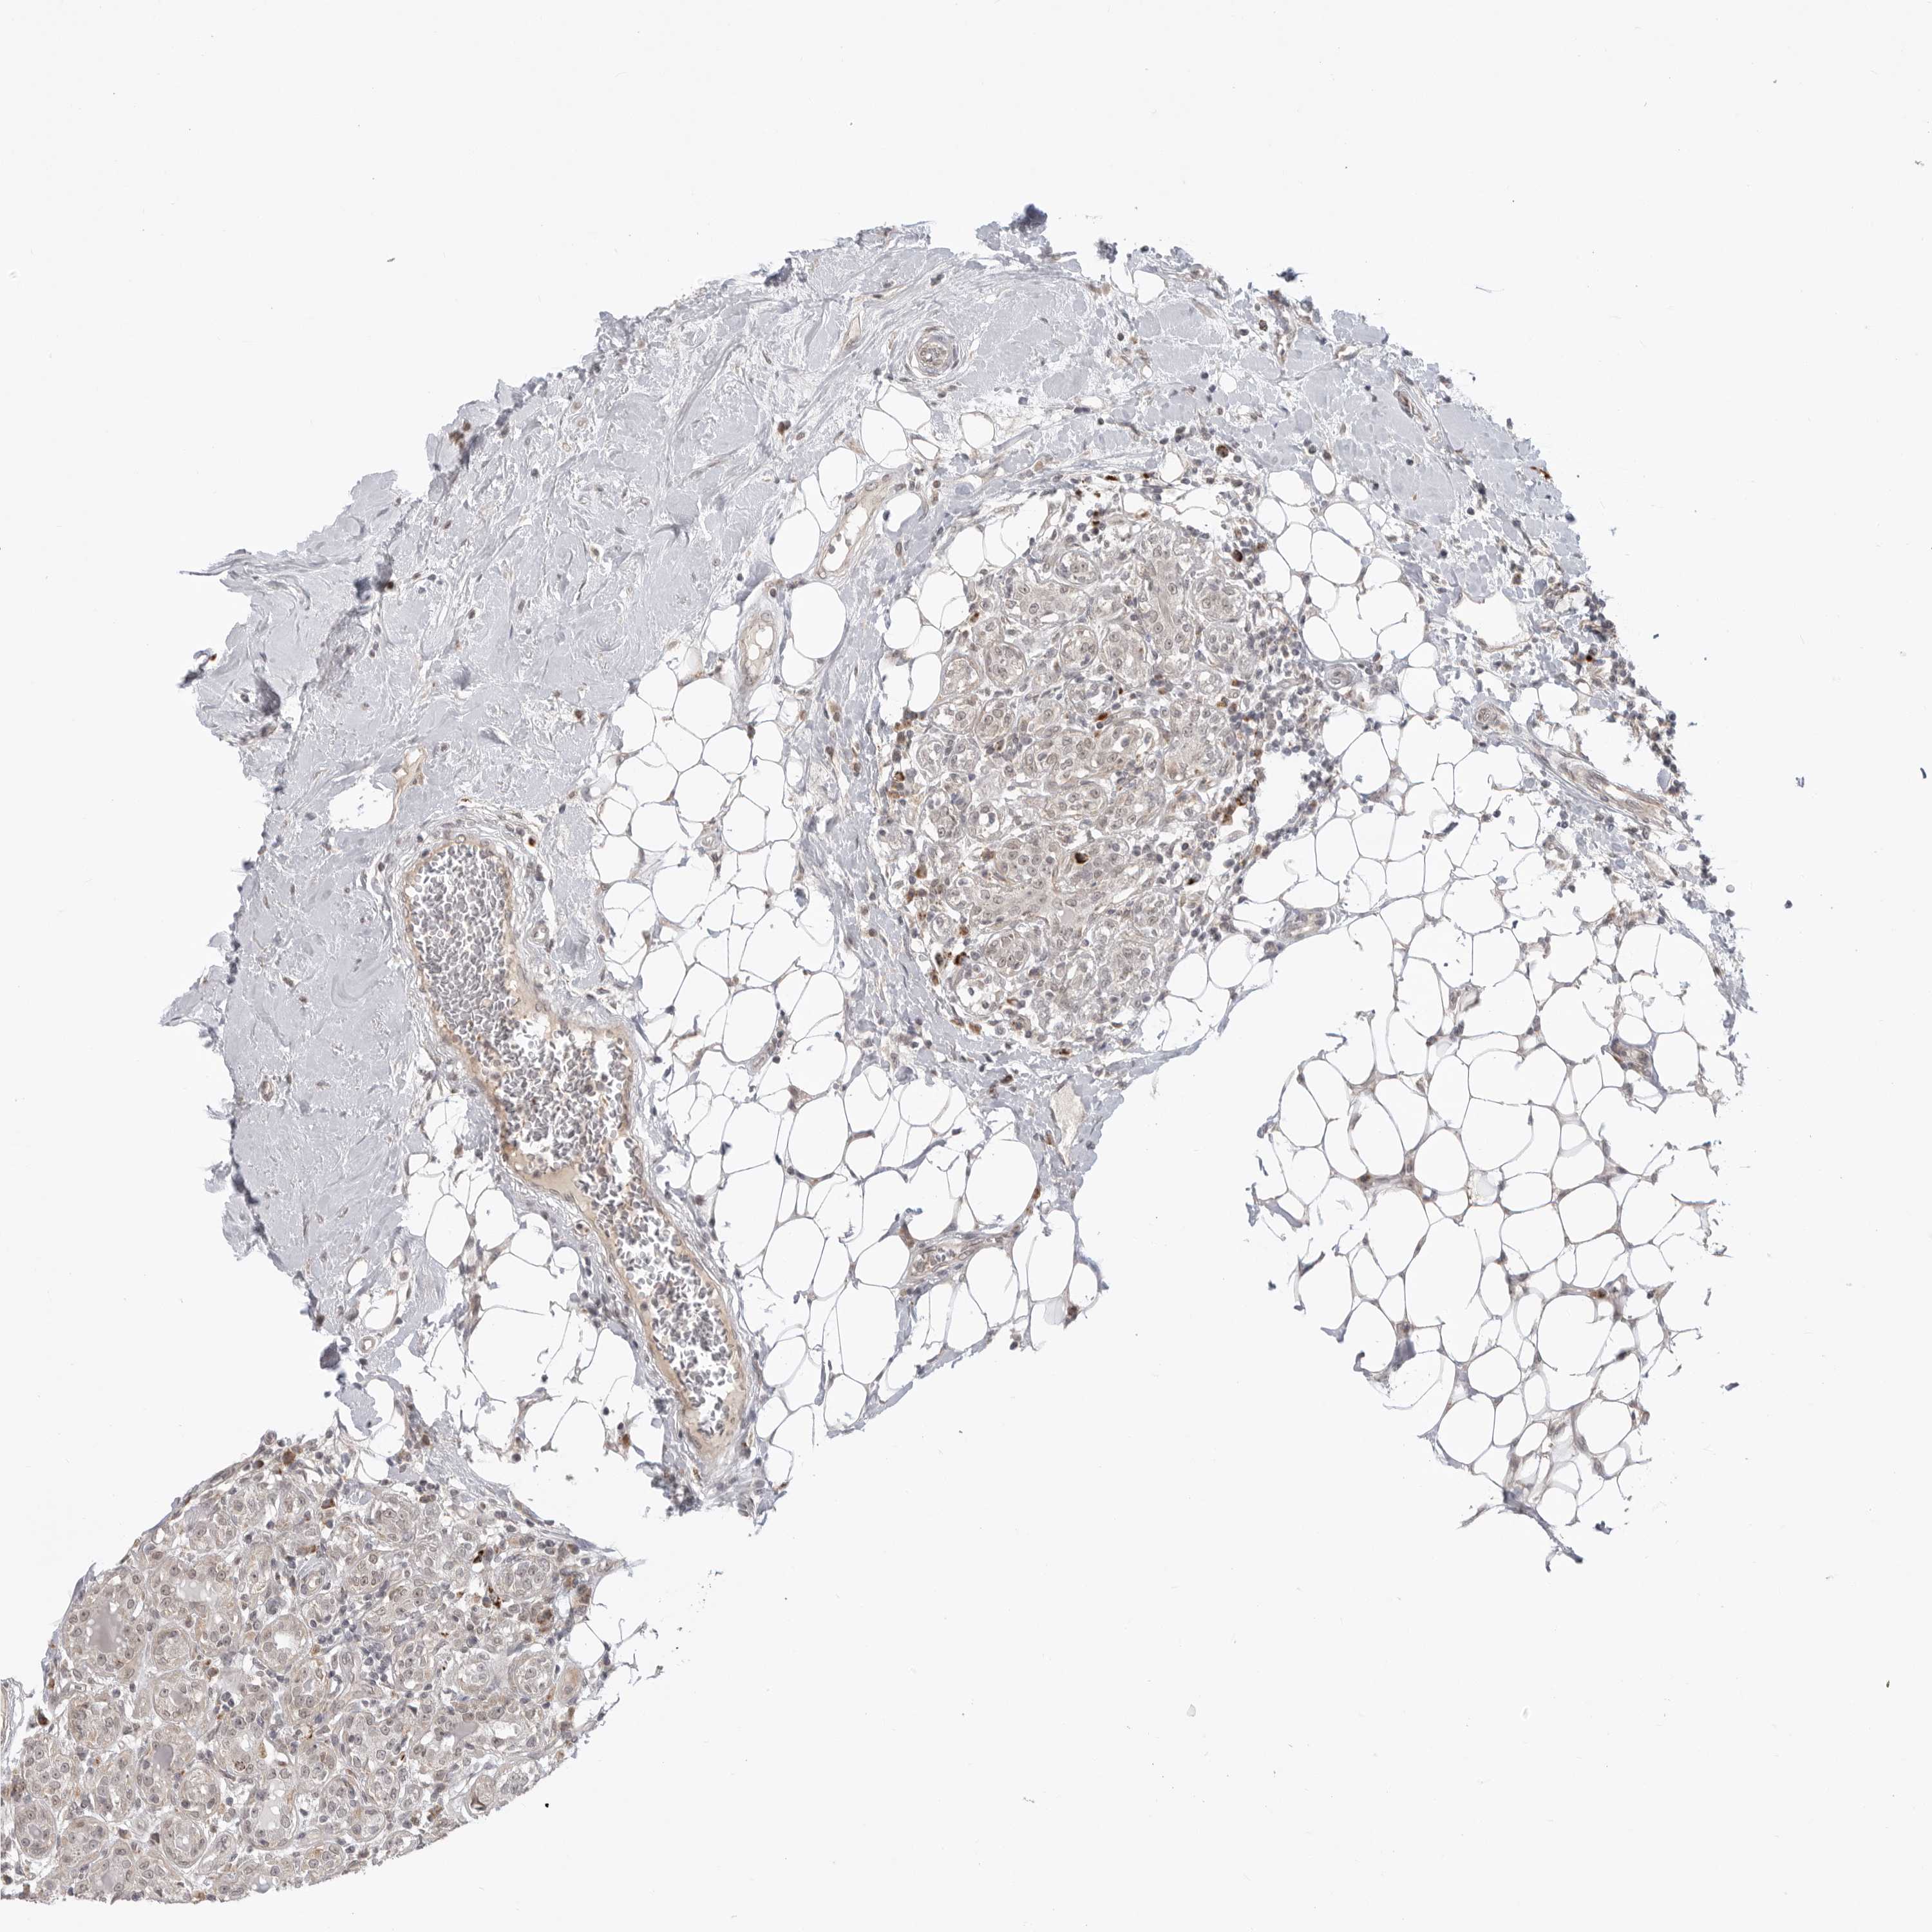

BRCA TCGA BRCA VALIDATION PROTEIN EXPRESSION